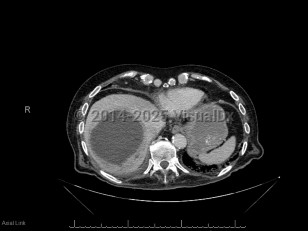

Intraabdominal abscessIntraabdominal abscess